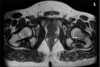

Figure 2

PD transverse T2-weighted image of left hip showing bone marrow edema (arrow)